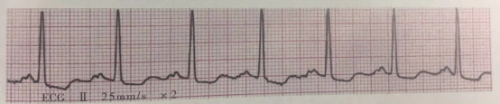

4.阵发性室上性心动过速的心电图表现

(1)相当于一系列连续很快的房性或交界性早搏,频率150~250/分,节律规则。

(2)QRS波群形态基本正常,时间≤0.10s。

(3)ST-T无变化,或发作时S-T段下移和T波倒置。